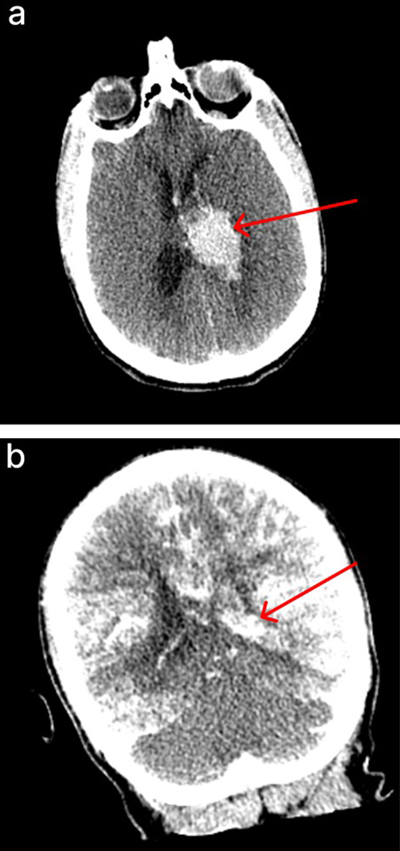

In four of the cases in which herniation of tissue through the spinal canal was observed, we had CT scans of the brain following perfusion available, which we analyzed further. In one of these cases, there was evidence of a midline shift; however, this donor had a history of an arteriovenous malformation in the frontal lobe, and no pre-perfusion CT scan was available for comparison, so the arteriovenous malformation may have been present before the perfusion. In another case, the donor died of an aneurysm, which is visible on the CT scan, but there was no midline shift and the ventricles were of normal size. In another case, the brain appeared to have smaller-than-normal ventricles, but there was no midline shift, and there was no pre-perfusion CT scan available for comparison. Finally, in one of these cases, the donor died from a hemorrhagic stroke, and there was a large clot visible on the pre-perfusion CT scan, but after perfusion, there was no change in the ventricles or evidence of midline shift (Figure 7). Taken together, these results are difficult to interpret, because many of the cases in which herniation occurred had a history of brain pathology, which may be a predisposing risk factor for herniation. However, our data suggests that the herniation event does not necessarily lead to significant changes in the anatomical condition of the brain as visualized on CT.

Figure 7.

CT scans of a brain donor with observed herniation of tissue through the spinal canal during perfusion, without no clear evidence of significant anatomical sequelae. a: Pre-perfusion axial CT image of a donor with a known hemorrhagic stroke, showing a large intraventricular clot (red arrow). b: Post-perfusion coronal CT image showing partially successful perfusion, as evidenced by iohexol distribution, with persistent intraventricular clot (red arrow). During perfusion of this brain, a suspected herniation event occurred, as tissue abruptly emerged from the spinal canal, prompting immediate termination of the perfusion. However, there was no clear evidence of anatomical damage due to the herniation on the CT scan, as the ventricles remained of the same size and no midline shift was observed. Donor ID 179, PMI of 70.5 hrs.